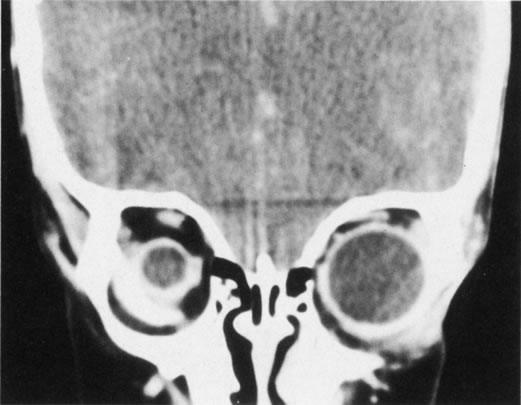

Hypertelorism is often associated with a variety of facial clefts, craniosynostosis, and meningoencephaloceles. The normal distance between the orbits is roughly 16 mm at birth and increases to 25 to 28 mm in adults.15 A widening of the anterior ethmoid air cells is believed to be the main anatomic defect responsible for primary orbital hypertelorism, resulting in an increase in soft tissue, bone, and cartilage between the medial canthi.16 The posterior ethmoid air cells and the sphenoid bone are usually normal, and as a result, the optic foramina are usually normal as well. The cribriform plate is not widened but can be depressed 10 mm below its usual level, making the extracranial approach to the correction of this defect hazardous. The angle between the central axes of the orbits is normally 45°. In orbital hypertelorism, the axes of the orbits are more divergent, measuring up to 60° in severe cases.